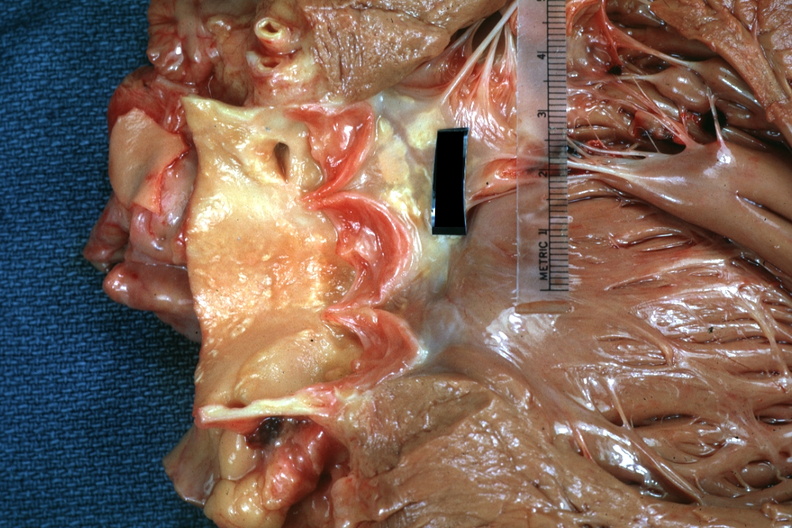

GROSS: CARDIOVASCULAR: HEART: Left Coronary Artery Origin In Aortic Arch: Gross natural color high origin of coronary well shown heart is enlarged

GROSS: CARDIOVASCULAR: HEART: Left Coronary Artery Origin In Aortic Arch: Gross natural color high origin of coronary well shown heart is enlarged